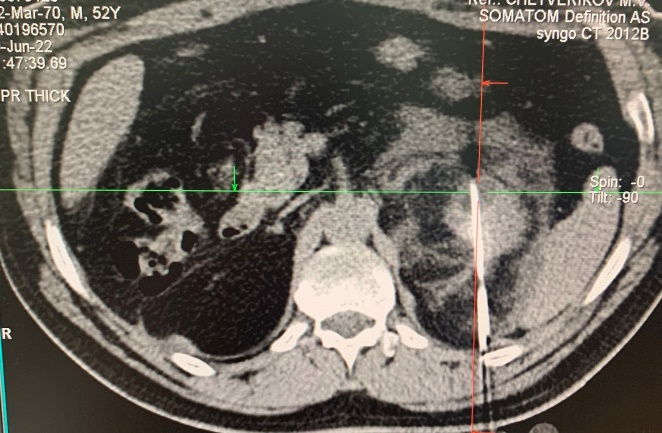

Проведен ретроспективный анализ эффективности криоаблации с 2015 по 2025 гг. у 630 пациентов больных с ПКР находящихся на лечении в ГБУ РО КДЦ «Здоровье». Возраст больных варьировал от 41 до 82 лет (средний возраст 61,5 лет). Из них 346 женщин, 284 мужчин. Критериями выбора методики криоаблации являлись наличие коморбидного статуса, конституциональные особенности и сопутствующая соматическая патология, которые ограничивали возможность выполнения органосохраняющей резекции или радикальной нефрэктомии. При этом все пациенты, независимо от возраста и пола, имели стадию T1aN0M0, а их функциональный статус по шкале ECOG составлял 0–1. Диагноз был установлен на основании клинико-рентгенологических данных (КТ почек с контрастным усилением) в соответствии с рентгенологическими критериями диагностики ПКР. Гистологическое подтверждение диагноза получали у 587 (93%) больных, остальные случаи признавались ложноотрицательным результатом. Единственная почка была у 5 больных, у 3 больных был билатеральный ПКР, в последующем такие больные получали комбинированное хирургическое лечение (рис. 3, 4).

Рисунок 3 - Снимки больного с билатеральным ПКР (до лечения)